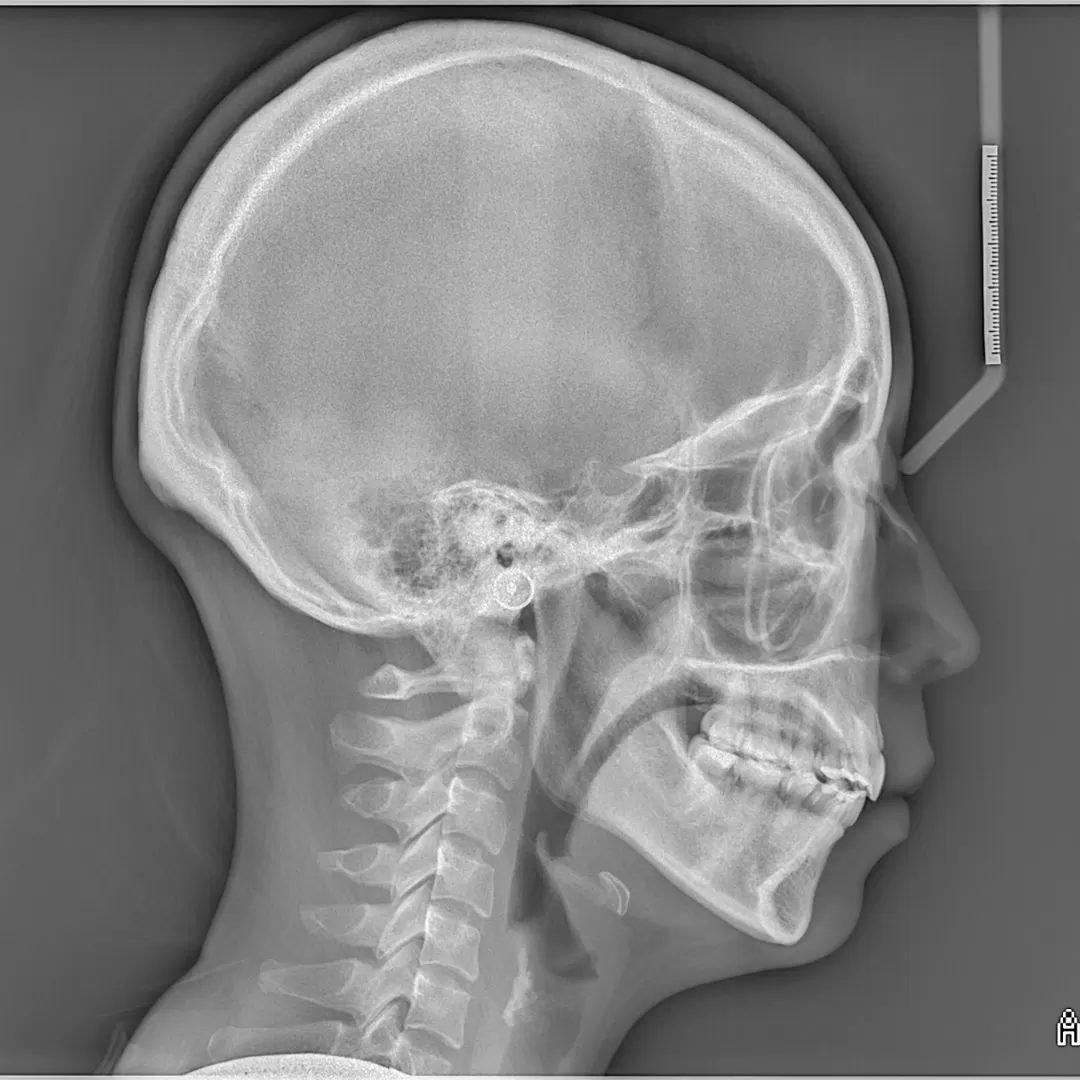

こちらをご覧ください。

かなりの前突と奥歯の噛み合わせの低下による、顎関節の圧迫が

見受けられる症例です。

術後を見てください。

前歯がひっこんだ!というのは短絡的です。

当然、顔面の変化はかなりあったでしょう。

奥歯の噛み合わせの上昇がみられていること、

また噛む位置の変化がおきていることで、顎関節の正常化も

見られているのです。

顎関節の正常化はお顔の歪みの正常化につながります。